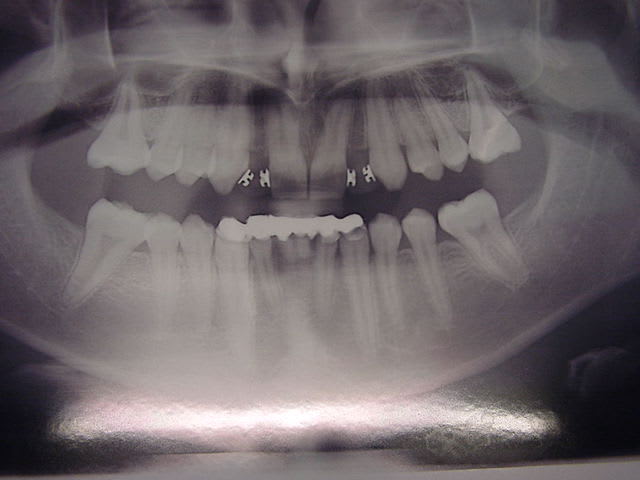

bonjour, le cas :

Dsc00091 vo4p11 - Eugenol

ceci par exemple

Dsc00090 mq4djg - Eugenol

Dsc00089 nurt6y - Eugenol

préparations pour bridge collé ...des commentaires?

Dsc00088 s3ie5k - Eugenol

Dsc00092 jmfmzu - Eugenol